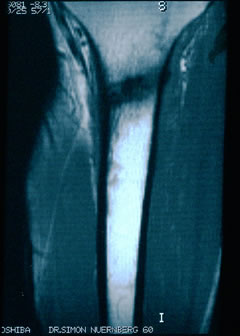

Also hab ich das entsprechende Kernspin-Bild meines Schienbeines nach dem Ironman wieder heraus gekramt. Und hab mir den "Haarriss" noch mal angeguckt. Haarriss? Ich seh da eine Lücke. Und kann mich an die Schmerzen sehr, sehr gut erinnern.